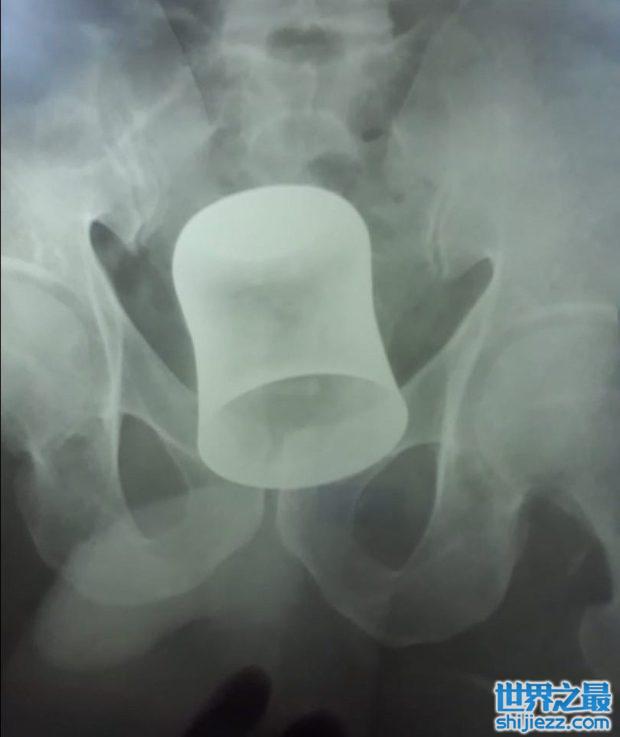

而据美国消费者安全委员会的数据表示,直肠是最多人把异物收纳进去的地方。像是啤酒罐、圣诞节挂饰、药瓶、雪茄管,甚至是一整尊的巴斯光年。这些都曾经是急诊室的医生,从病患的屁屁里面拿出来的诡异物品。

而且在印度还有一位62岁的男子,因为肚子疼痛不已就医,没想到医生竟然在他肠子里面,找到一个21厘米高的钢杯。而男子回想之后,认为他在几天前被歹徒抢劫过,而他在意外的当下被打昏,接着醒来以后屁股跟腹部都有疼痛感,认为是歹徒所为。